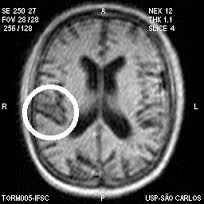

O acidente vascular cerebral é causado pela falta de circulação ou por uma hemorragia no tecido encefálico.

Cerca de 80% dos casos de AVC são do tipo isquêmico — os outros 20% são hemorrágicos.